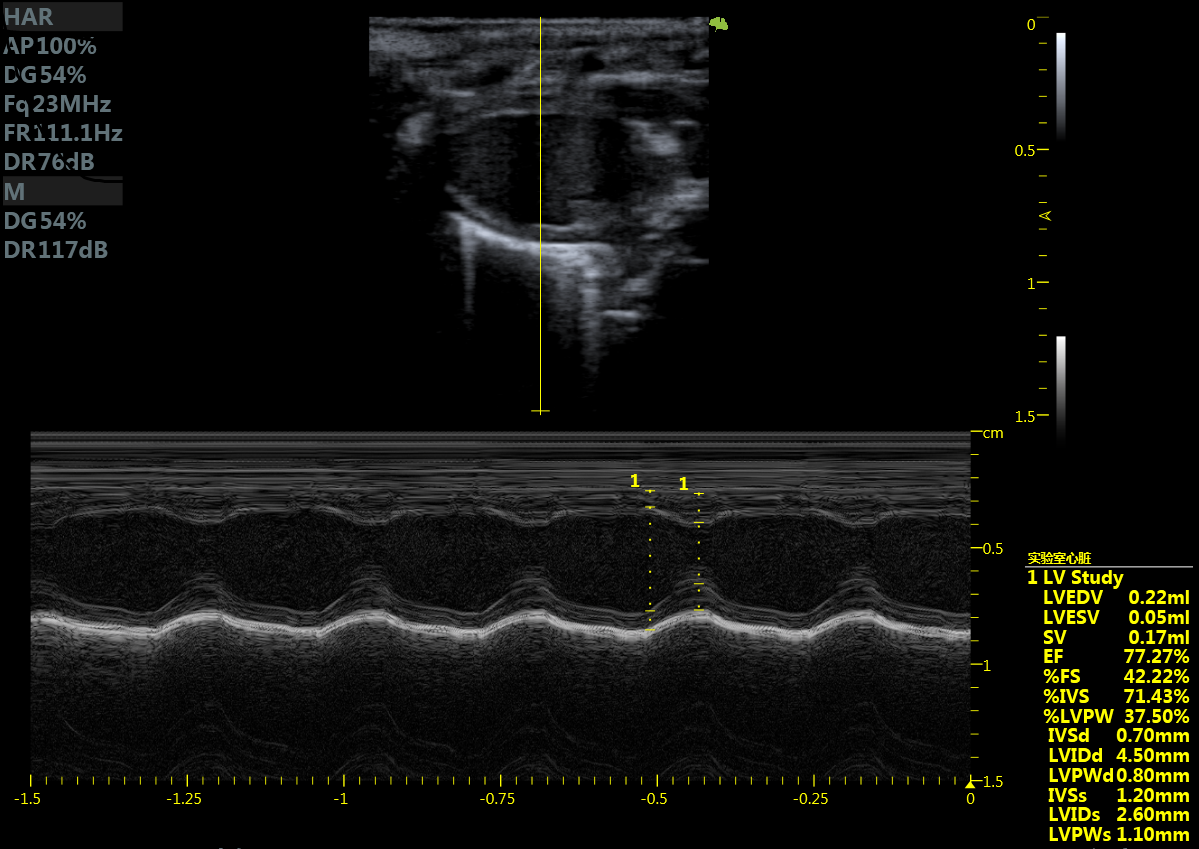

齐全的功能模块 :心脏测量包

小鼠长轴M型 小鼠短轴M型

小鼠长轴B型 小鼠短轴B型

大鼠短轴M型 大鼠长轴M型